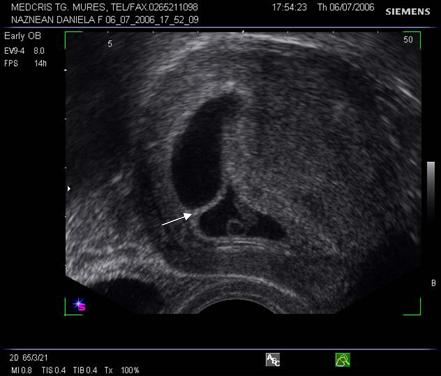

Fig nr 38. Sarcina biamniotica bichoriala 6 sapt . dupa

inseminare intrauterina cu stimulare ovariana, cele doua sageti marcheaza zona

de nidatie, respectiv placentatie, iar sacii amniotici sunt evident separati,

cu cate un embrion